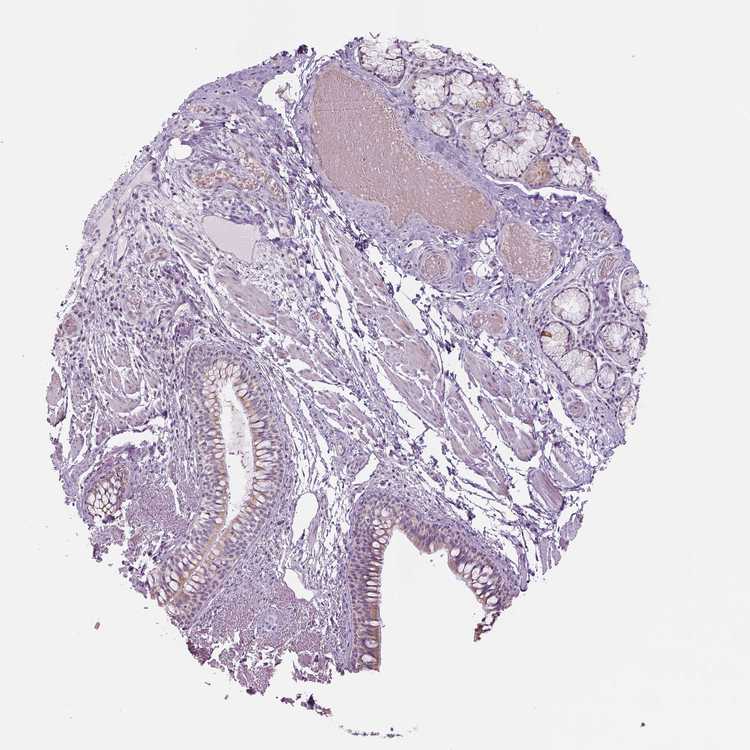

SOFT TISSUE 1 - Antibody stainingi

Antibody staining in the annotated cell types in the current human tissue is reported as not detected, low, medium, or high, based on conventional immunohistochemistry profiling in selected tissues. This score is based on the combination of the staining intensity and fraction of stained cells.

Each image is clickable and will lead to virtual microscopy that enables deeper exploration of all samples and also displays staining intensity scores, fraction scores and subcellular localization as well as patient and tissue information for each sample.

Antibody HPA018897Antibody HPA074629

Fibroblasts Not detectedNot detected

Peripheral nerve Not detectedNot detected